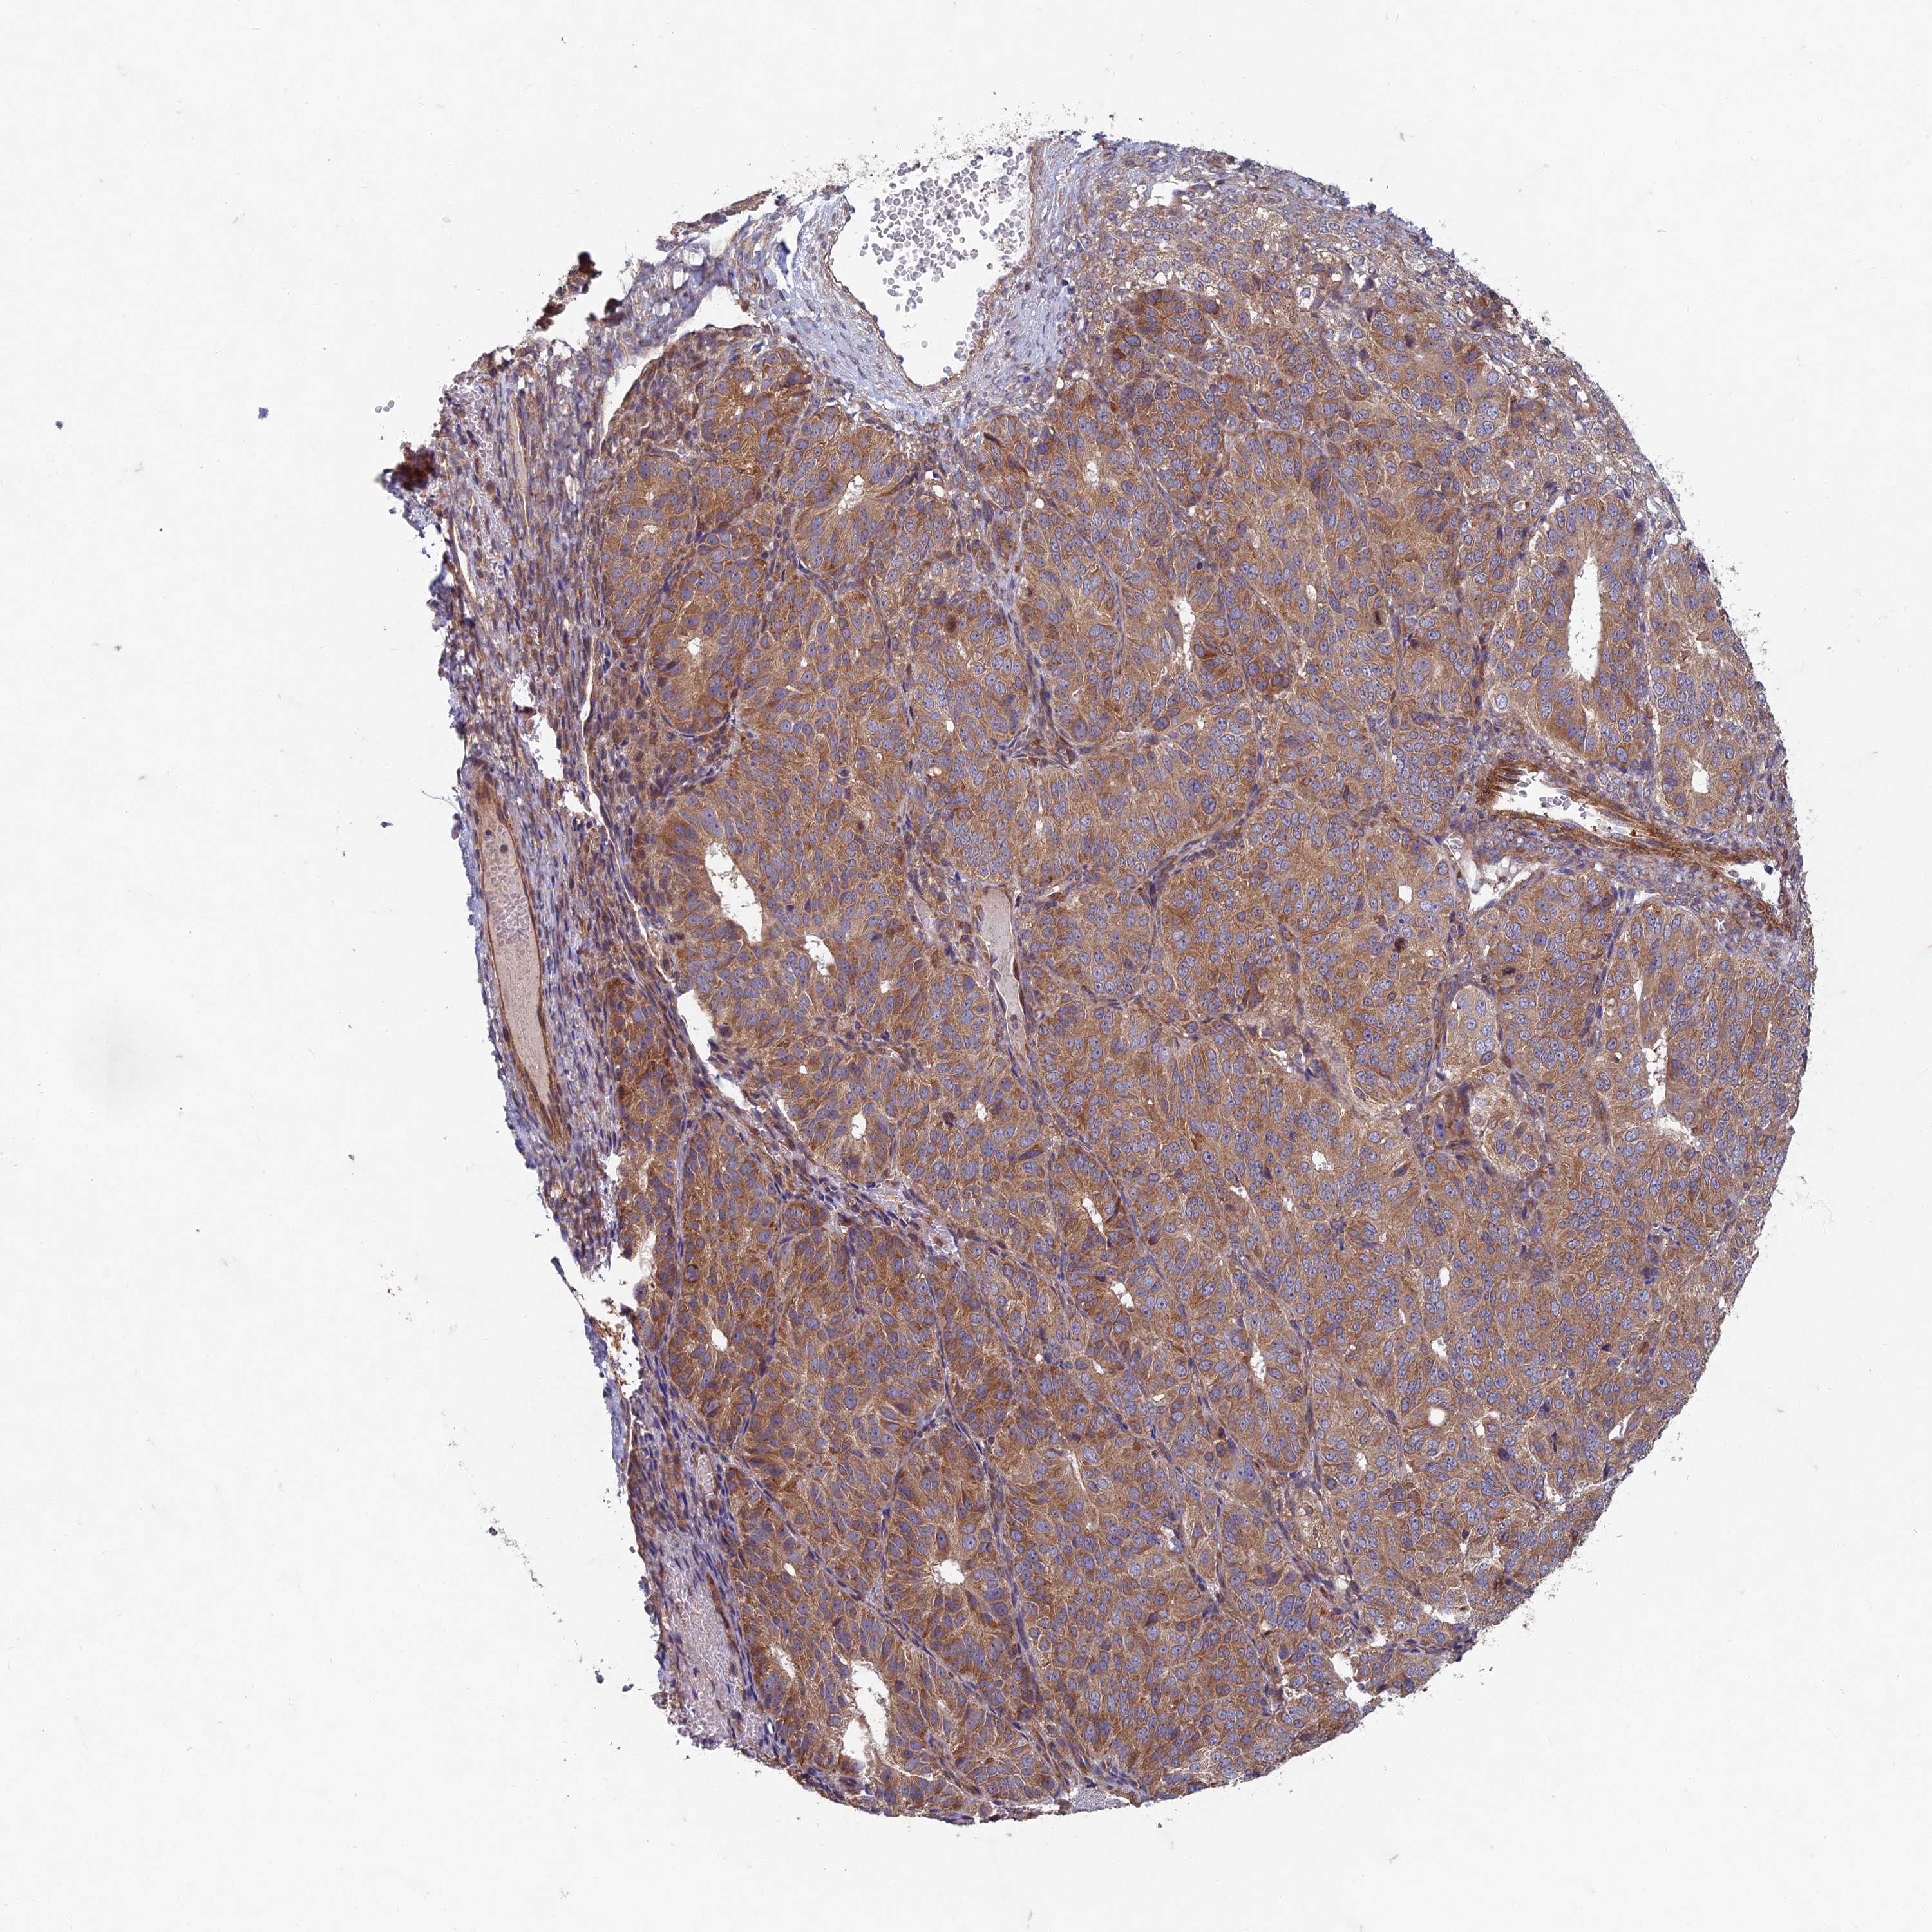

OVARIAN CANCER - Protein expressioni

A mouse-over function shows sample information and annotation data. Click on an image to view it in a full screen mode. Samples can be filtered based on level of antibody staining by selecting one or several of the following categories: high, medium, low and not detected. The assay and annotation is described here.

Note that samples used for immunohistochemistry by the Human Protein Atlas do not correspond to samples in the TCGA dataset.

Antibody stainingi

Antibody staining in the annotated cell types in the current human tissue is reported as not detected, low, medium, or high, based on conventional immunohistochemistry profiling in selected tissues. This score is based on the combination of the staining intensity and fraction of stained cells.

Each image is clickable and will lead to virtual microscopy that enables deeper exploration of all samples and also displays staining intensity scores, fraction scores and subcellular localization as well as patient and tissue information for each sample.

Antibody HPA039613

Staining

High

Medium

Low

Not detected

Intensity

Strong

Moderate

Weak

Negative

Quantity

>75%

75%-25%

<25%

None

Location

Nuclear

Cytoplasmic/membranous

Cytoplasmic/membranous,nuclear

Cystadenocarcinoma, serous, NOS

Carcinoma, endometroid

Cystadenocarcinoma, mucinous, NOS

Carcinoma, NOS